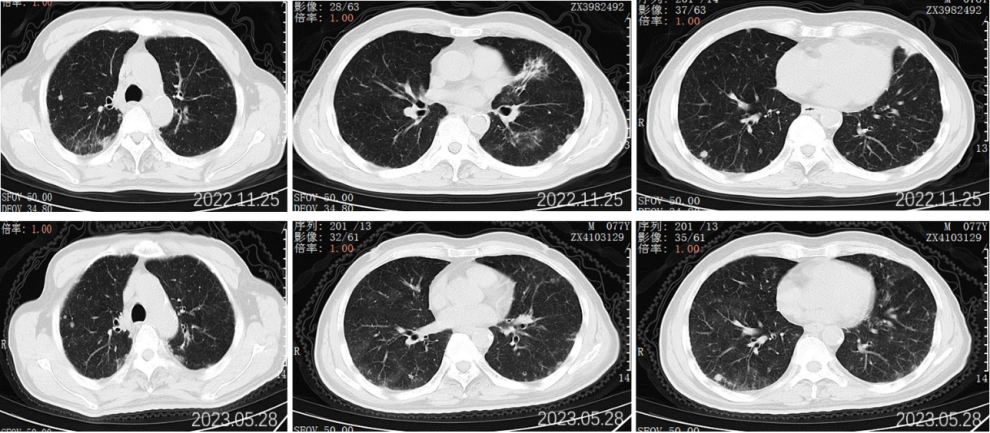

2022.11.25胸部CT平扫:对比2022-09-27影像:1.新见两肺多发间质性肺炎样改变,感染考虑,VP-RADS 2类;2.两肺多发小结节、类结节影,部分较前略缩小,转移性考虑;3.左侧第5后肋骨质破坏,相仿。

2022.11.25腹部CT增强:肝胆管细胞癌治疗后复查:对比2022-09-27日:1、肝右叶多发占位,较前大小相仿,目前仍可见活性;2、肝内及双肾多发小囊肿,相仿;肝S2段小血管瘤考虑,相仿;3、慢性胆囊炎改变;4、肝内钙化灶;前列腺钙化灶。

2023.5.28胸部CT平扫:对比2022-11-25片:1.两肺散在多发炎症,较前相仿,VP-RADS 2类;2.两肺多发小结节、类结节影,转移瘤考虑,较前相仿;3.左侧第5后肋骨质异常,相仿。男性乳腺发育。

2023.5.28腹部CT增强:肝胆管细胞癌治疗后复查:对比2022-11-25日:1、肝右叶多发占位,较前相仿;2、肝内及双肾多发小囊肿,肝S2小血管瘤,大致相仿;3、慢性胆囊炎改变;胆囊内点状结石未见显示;4、肝内钙化灶;前列腺钙化灶。